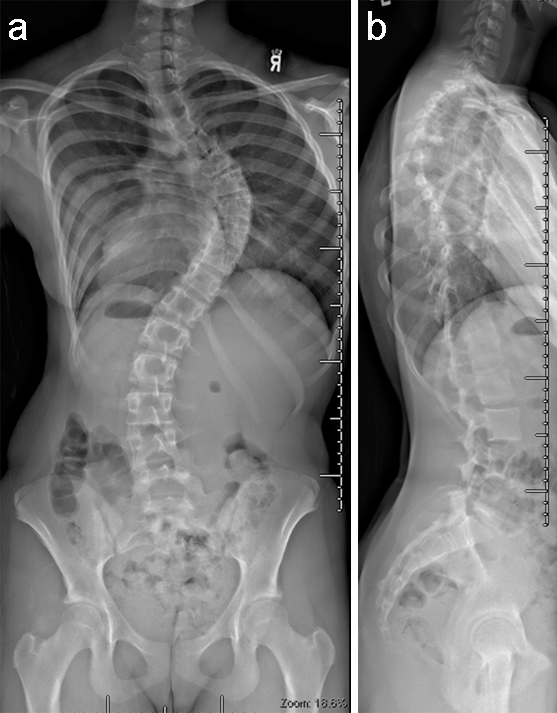

(Case provided by Firoz Miyanji, BC Children's Hospital, Vancouver, BC, Canada)

A 12-year-old girl with AIS underwent T2-T12 posterior spinal instrumentation and fusion.